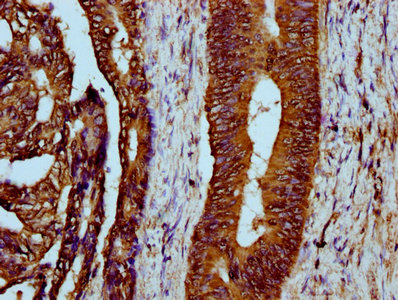

IHC (Immunohistochemistry)

(IHC image of AAA234887 diluted at 1:300 and staining in paraffin-embedded human colon cancer performed on a Leica BondTM system. After dewaxing and hydration, antigen retrieval was mediated by high pressure in a citrate buffer (pH 6.0). Section was blocked with 10% normal goat serum 30min at RT. Then primary antibody (1% BSA) was incubated at 4 degree C overnight. The primary is detected by a biotinylated secondary antibody and visualized using an HRP conjugated SP system.)